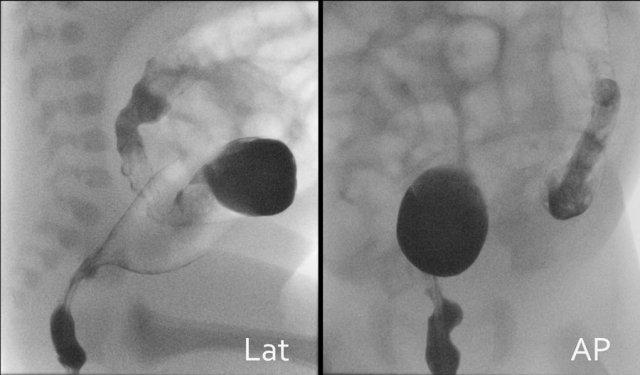

Hình ảnh tư thế nghiêng của trực tràng và đại tràng sigma cần được ghi nhận trước, tiếp theo là hình ảnh tư thế thẳng.

Tập trung vào đường kính trực tràng so với phần còn lại của đại tràng, sự hiện diện của đại tràng nhỏ và các hạt phân su.

Trong bệnh Hirschsprung, chỉ cần xác định chiều dài đoạn ruột bị tổn thương là đủ, nhưng trong các bệnh lý khác, cần cố gắng làm đầy thuốc đến hồi tràng tận, vì tắc nghẽn có thể nằm ở hồi tràng.

Bắt đầu thụt tháo ở tư thế nằm nghiêng để đánh giá trực tràng.

Lưu lại các hình ảnh cine từ lần bơm thuốc cản quang đầu tiên, vì khi bơm thêm thuốc, các dấu hiệu có thể bị che khuất do ruột giãn quá mức.

Bình thường trực tràng phải rộng hơn đại tràng sigma.

Hình ảnh cho thấy chỉ số trực tràng-sigma bất thường <1.

Đây là một trường hợp khác của bệnh Hirschsprung.

Chẩn đoán xác định bệnh Hirschsprung được khẳng định bằng sinh thiết.